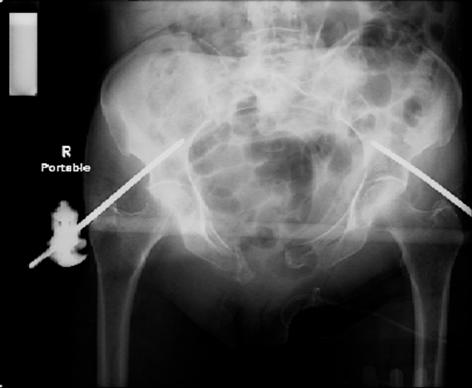

pt treated that night with I/D and supra-acetabular frame to close the ring. consideration was given for SI screws bilateraly, but given time of night and other factors decision made not to proceed.

so the question is what next operatively if anything? concerns are infection, nonunion anteriorly and possible incompetence of the pelvic floor which may lead to prolapse issues. right rami are comminuted and plating may entail ilioinguinal approach to extend plate laterally to right iliac wing. retrograde screw up right rami is an option but I am not convinced it will add much. adding SI screws very doable, but major concern is restoring anterior ring. so far wound is clean and closed over a drain, and I have no plans to open it back up and wash again.

maintaining pelvic alignment in ex-fix in 70 yo female for any length of time may be challenging.